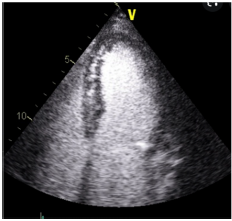

A respeito da técnica demonstrada na imagem a seguir,

assinale a afirmativa correta.